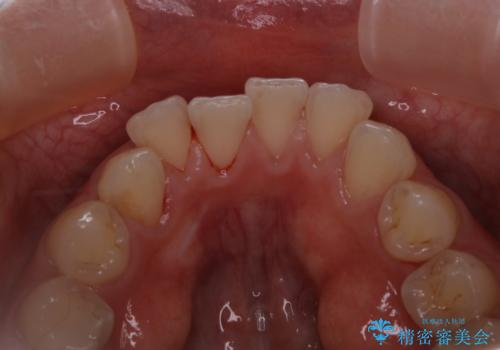

インビザラインのアタッチメントをつける前にPMTC

- インビザラインでの矯正治療中で、アタッチメントの設定前にきれな状態にしたいとのことでした。PMTC30分コースを行いました。

マウスピース矯正インビザライン治療では、歯の表面にアタッチメントという突起を設定します。(アタッチメントは歯の動きを効率的に移動するためのものです)

アタッチメントの設定時に、プラークや歯石・着色がついていると精密に付かないことや、外れやすくなることがあります。

PMTCを行い、専門的な機械でしっかりと汚れを除去してからアタッチメントの設定をすることがおススメです。